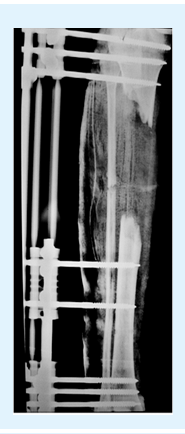

• Example

skin5

Description

Circumferential bone loss of more than 4 cm

5